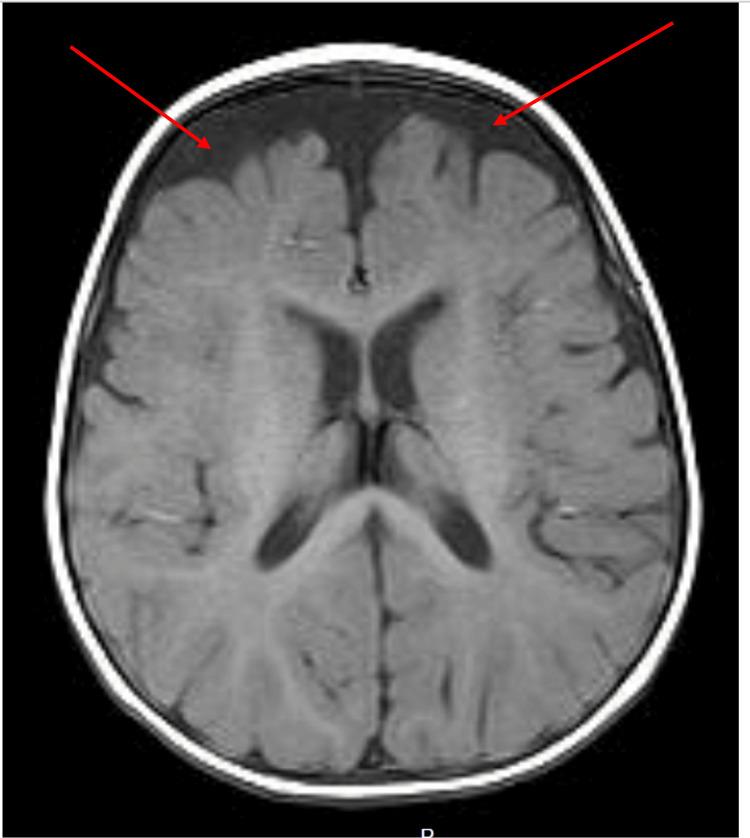

The rare ARV1 gene encodes a protein that is crucial for homeostasis and sterol metabolism. It is vital for maintaining membrane integrity and cellular stability. Given the limited epidemiological data, it is evident that ARV1 mutations are rare, showing significant neurological and systemic manifestations, including developmental delays, epilepsy, or cardiomyopathy. We report a case of a six-month-old female presenting with global developmental delay, hypotonia, and poor fine motor milestones. MRI revealed bifrontal subarachnoid spaces and abnormalities in the right parietal lobe. A homozygous pathogenic variant in the ARV1 gene (p.Phe144Argfs*5) was confirmed through whole exome sequencing (WES), thereby diagnosing autosomal recessive developmental and epileptic encephalopathy-38 (DEE38). Through this report, we aim to highlight the importance of early diagnosis in rare genetic disorders and increase awareness among healthcare professionals.

罕见的ARV1基因编码一种对体内平衡和固醇代谢至关重要的蛋白质。它对于维持膜完整性和细胞稳定性至关重要。鉴于流行病学数据有限,很明显ARV1突变很少见,会表现出明显的神经和全身表现,包括发育迟缓、癫痫或心肌病。我们报告一例6个月大女性病例,表现为全面发育迟缓、肌张力减退和精细运动里程碑发育不良。MRI显示双侧额叶蛛网膜下腔及右侧顶叶异常。通过全外显子组测序(WES)证实了ARV1基因中的一个纯合致病变异(p.Phe144Argfs*5),从而诊断为常染色体隐性发育性和癫痫性脑病38型(DEE38)。通过本报告,我们旨在强调罕见遗传病早期诊断的重要性,并提高医护人员的认识。